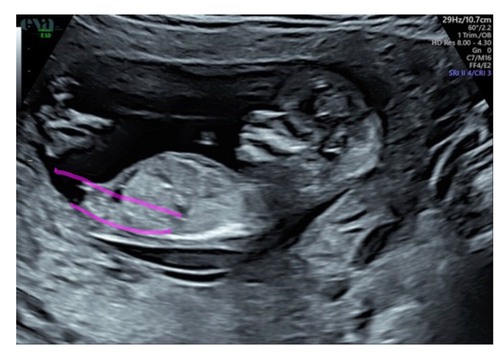

Wie o wie? 13,1

Dit is een meisje!

Zie lijnen getekend als voorbeeld :-)

Hier is de nub dus niet goed te zien. Meer het been = dus niet door het midden.

(Blaas wel mooi in beeld ;-))